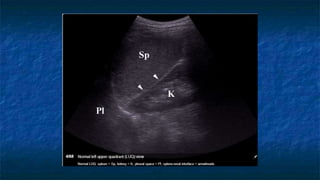

4)FAST: LUQ exam

 Probe placed

 Perpendicular

 Mid - coronal plane

 Just superior to the iliac crest

 Probe facing

 Towards patient’s head

 Evaluating

 Spleno-renal interface

 Possibility of fluid in splenorenal recess

and presplenic /subphrenic space( most

common space for fluid collection in

LUQ)